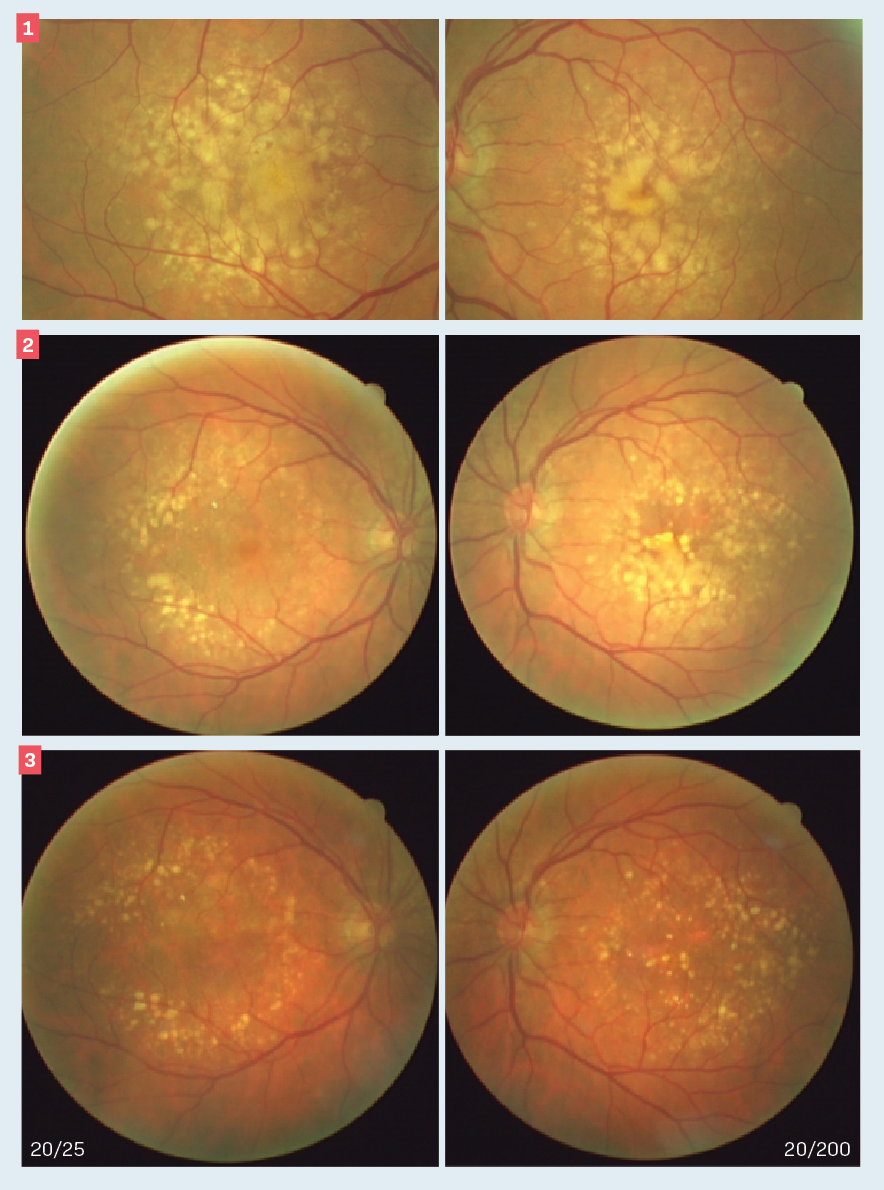

Mohammad Rafieetary, OD, FAAO, shares highlights from his SECO 2022 presentation titled "Image-in that! Scanning for retinal disease."

OCT showed inner retinal hyperreflectivity, diffuse retinal thickening with intraretinal fluid, and a serous macular detachment.